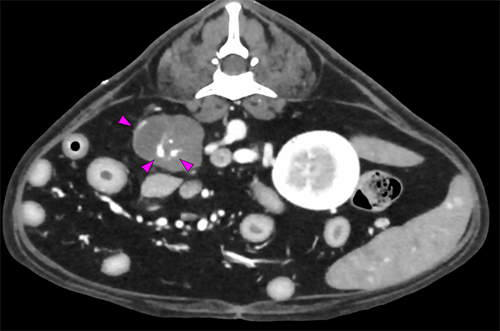

では、最後に後腹膜の血管肉腫の画像と肺転移の動画を!

フレンチ・ブルドッグ 12歳

右腎臓尾側・後腹膜血管肉腫疑い